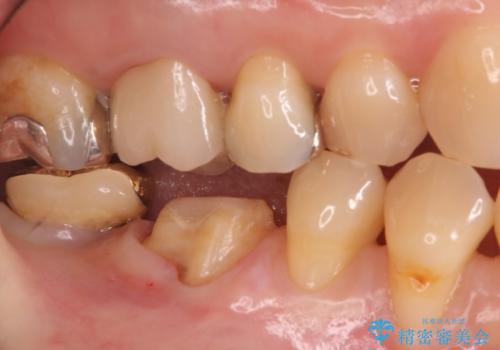

- 昔つめた材料が欠けたこと、歯の捻転を主訴に来院されました。

矯正治療の希望はなかったため、被せ物で歯の形を修正することになりました。

不適合だった詰め物の裏側に大きな虫歯がありました。

セラミックインレーやアンレーでは強度に不安が残るため、クラウンでの修復処置としました。

クラウンでは歯のがたつきを修正することもできます。

虫歯の除去と歯の捻転の両方を解決することができました。